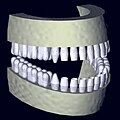

Rekonstruiertes 3D-Zahnmodel aus Daten eines DVT-Scans -